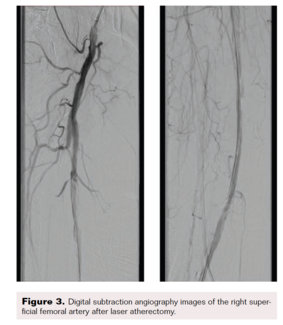

Patients with end-stage foot are commonly diabetic and/or have advanced chronic kidney disease. These patients are at very high risk for major amputation and generally are poor candidates for surgical revascularization due to poor target...